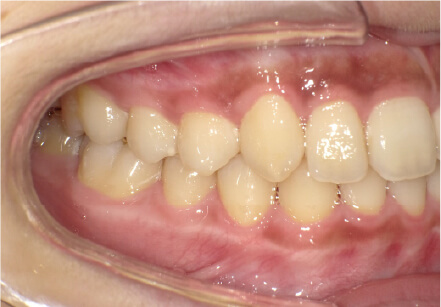

叢生の症例

17歳

女性

相談内容

カウンセリング・診断結果

治療内容・方法

全額アライナー矯正

術後の経過・現在の様子

クリアライナー使用

治療のリスク

痛み・歯根吸収・歯肉退縮・虫歯・後戻り

費用・治療期間

715,000円、2年10ヶ月